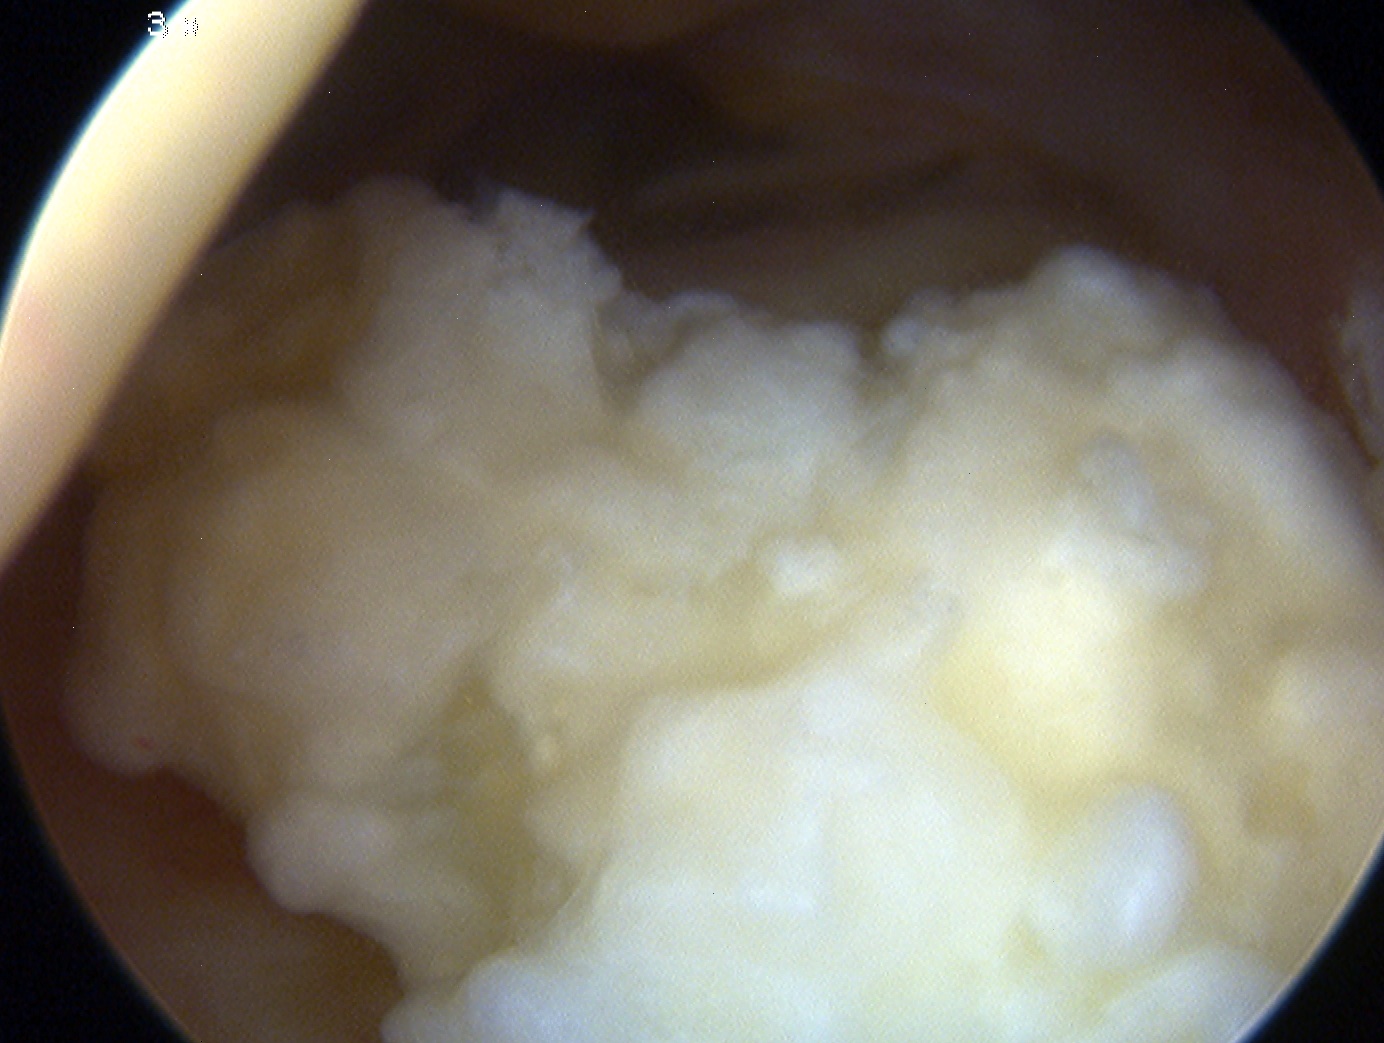

1. Removal Loose body

- synovial chondromatosis